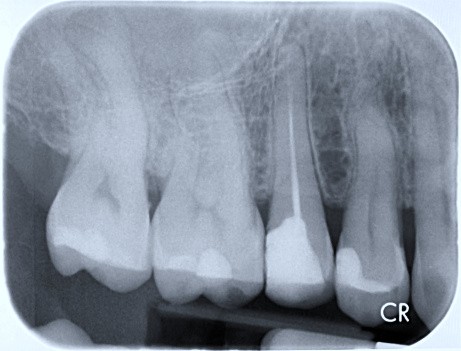

3 / 27

3. (Select ONE OR MORE correct answers)

What observation(s) can be made for tooth 1.5?